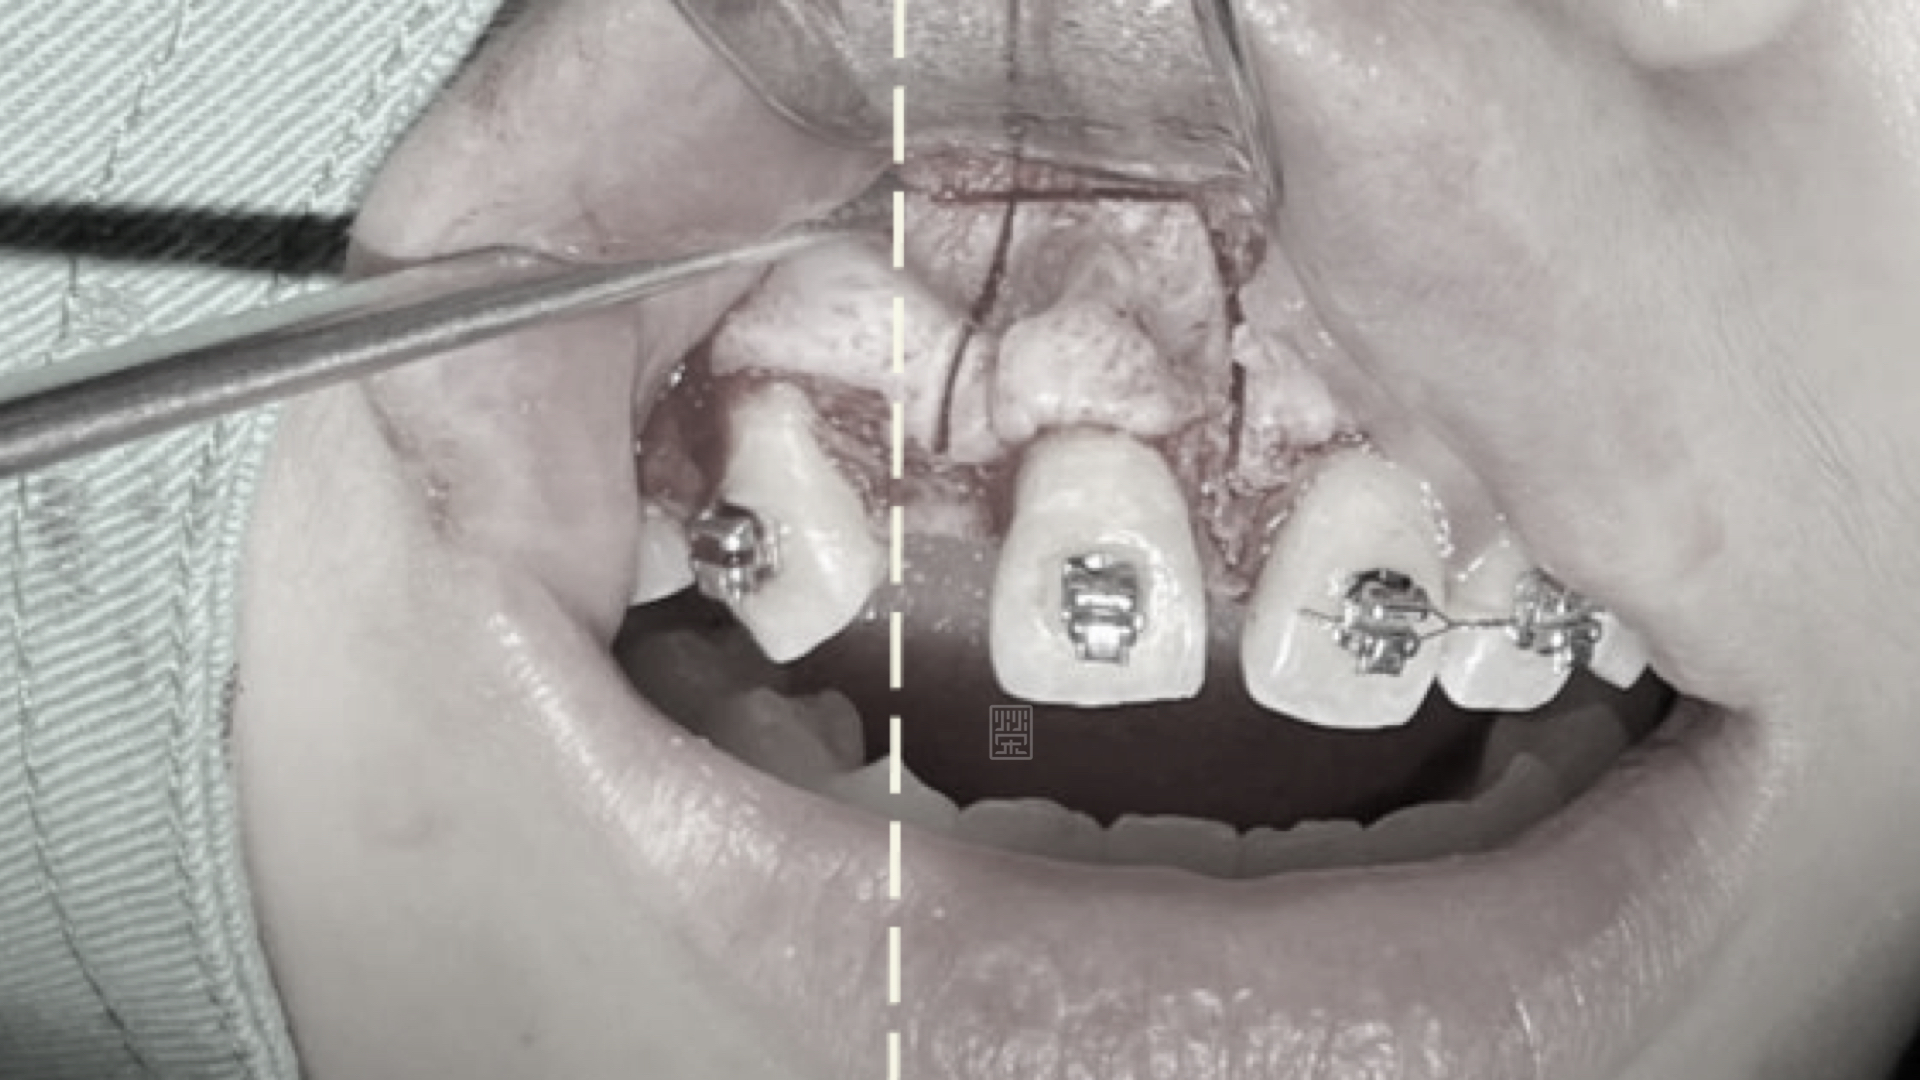

皮質骨切開手術增加牙齒移動

矯正時因牙齒沾黏骨頭無法移動

首先張馨文醫師先將牙齒重新排列,但是在門牙的部分因為先前外傷關係,牙齒發生沾黏的狀況,牙齒移動度很小,吳禕凡醫師藉由皮質骨手術加上術後立即施力,將門牙拉至中央位置,並且給側門牙植牙適當空間。